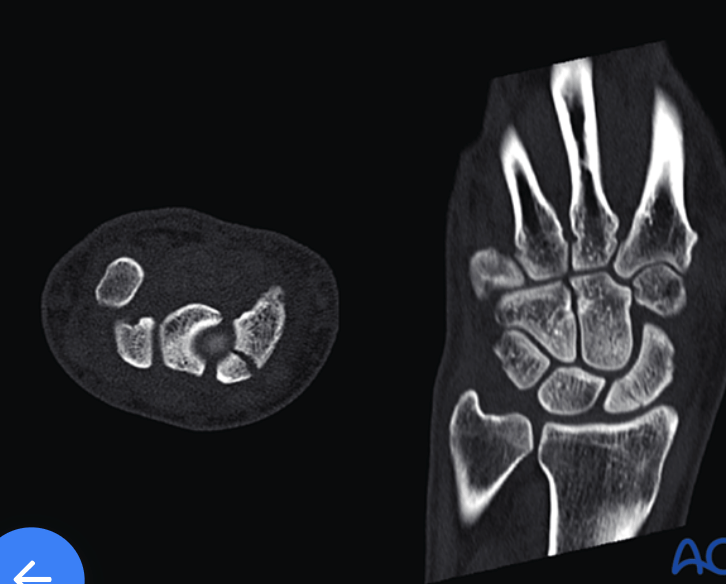

Exam with +Watson's Test. Describe treatment plan.

scaphoid with proximal pole fx: cannulated, headless, self-compressing screw (2.4 or 3.0 mm) fro large defects (5mm), anterograde via dorsal approach

+Watson's Test = pressure is applied to the scaphoid tubercle while the wrist is moved from ulnar to radial deviation; a positive result is a painful click, thud, or subluxation of the scaphoid as the pressure is released, indicating a tear in the scapholunate ligamen